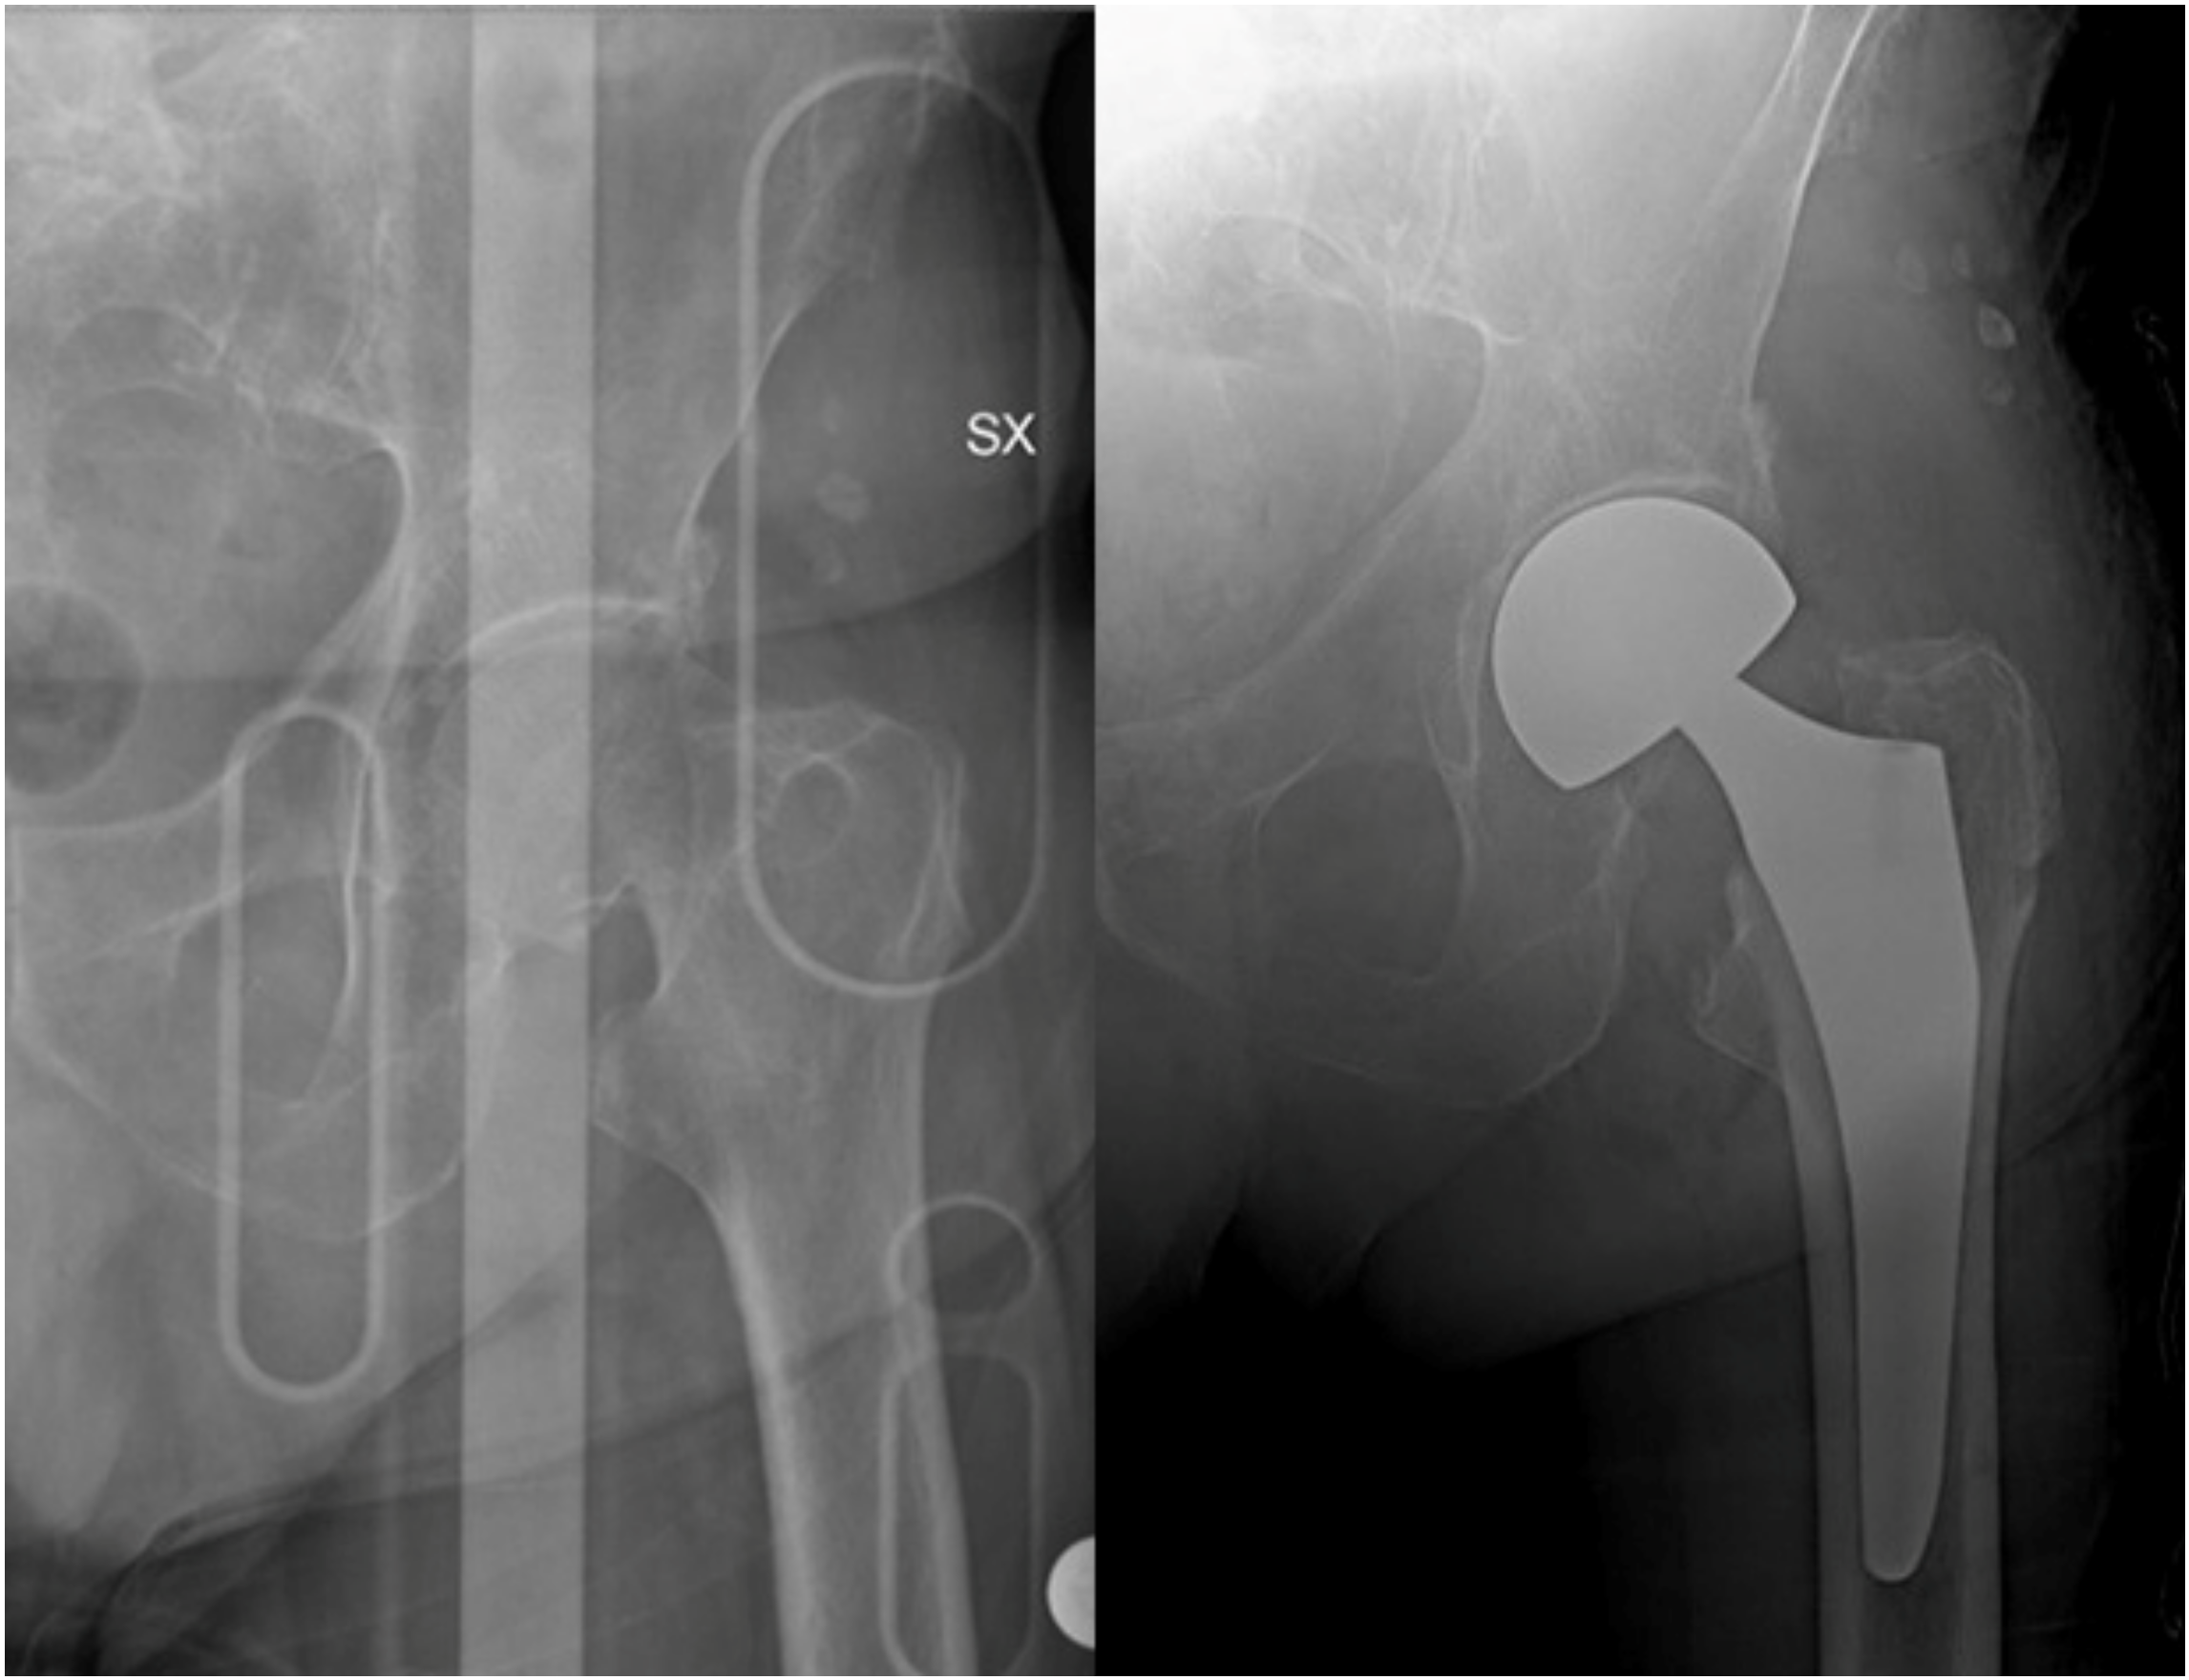

5. Surgical Management